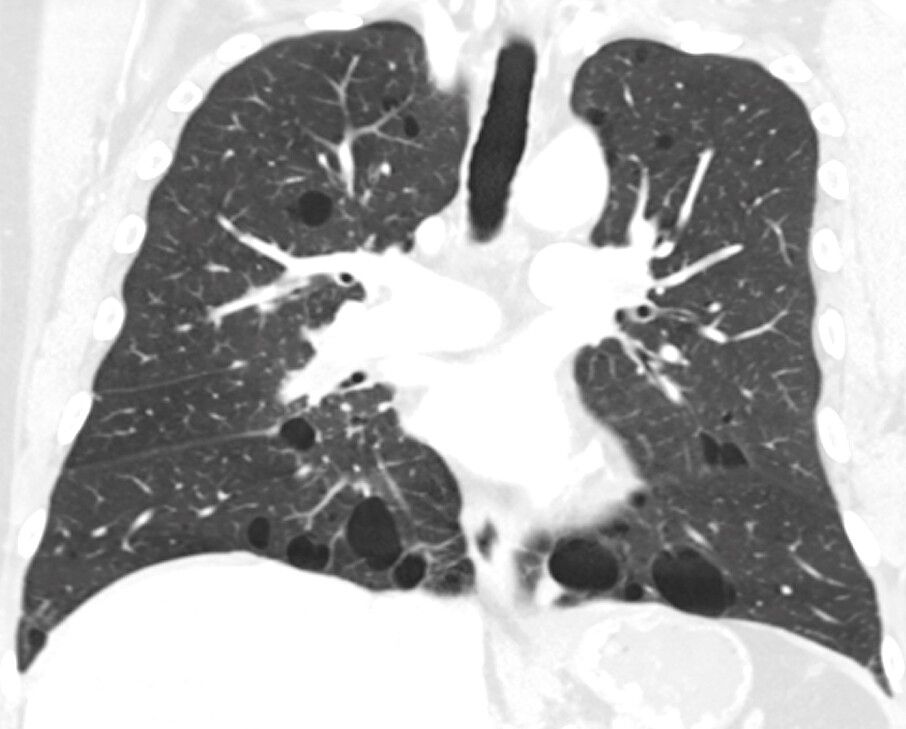

Birt-Hogg-Dubé syndrom také predisponuje jedince k rozvoji benigních cyst v plicích, opakovaným epizodám kolapsu plic (pneumotorax) a zvýšenému riziku rozvoje neoplazie ledvin. Birt-Hogg-Dubé syndrom je způsoben změnami (mutacemi) v genu FLCN (alias BHD) a dědí se jako autozomálně dominantní vlastnost.

Birt-Hogg-Dubé syndrom je charakterizován mnohočetnými nerakovinnými (benigními) kožními nádory, zejména na obličeji, krku a horní části hrudníku. Tyto výrůstky se obvykle poprvé objevují ve dvaceti nebo třiceti letech a postupem času se zvětšují a množí. Postižení jedinci mají také zvýšenou šanci na rozvoj cyst v plicích a abnormální hromadění vzduchu v hrudní dutině (pneumotorax), což může vést ke kolapsu plic. Kromě toho je syndrom Birt-Hogg-Dubé spojen se zvýšeným rizikem vzniku rakovinných nebo nerakovinných nádorů ledvin. I jiné typy rakoviny byly hlášeny u postižených jedinců, ale není jasné, zda jsou tyto nádory skutečně rysem Birt-Hogg-Dubého syndromu.

84% van de patiënten krijgt cysten in de longen, wat bij ongeveer 1/3e leidt tot een klaplong. Ongeveer 16-30% van de patiënten met Birt-Hogg-Dubé krijgt niercelkanker. Geen enkele patiënt met Birt-Hogg-Dubé is hetzelfde. De één krijgt 1 symptoom en de andere meerdere.

• Multiple, basale og bilaterale lungecyster uten annen klar årsak, med eller uten spontan primær pneumothorax